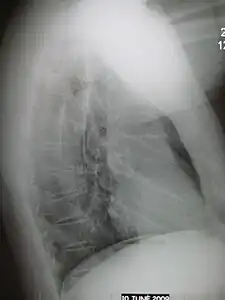

- Normal lateral CXR

- Right lower lobe pneumonia as seen on a lateral CXR